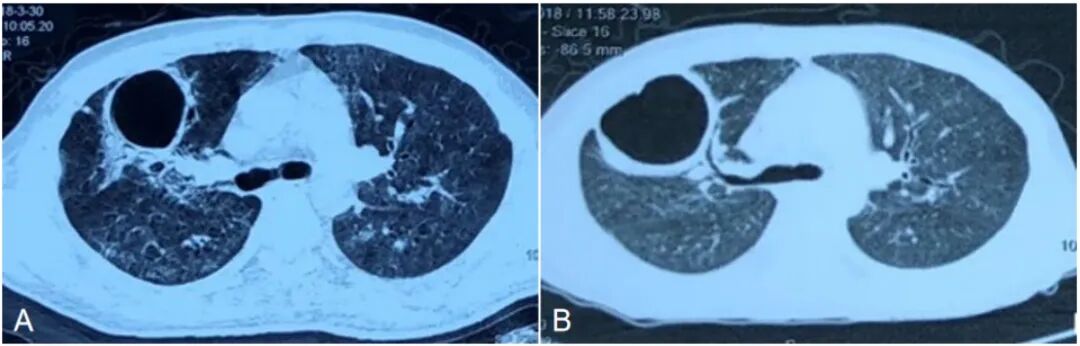

3  两次复查胸部CT均可见右上肺空洞病灶

出院后继续口服甲泼尼龙片及间断静脉使用环磷酰胺治疗,甲泼尼龙片由出院时48 mg逐渐减量为12 mg(7个月随诊),随诊7个月后复查胸部CT可见右上肺空洞消失(图4),患者一般情况稳定。

4  患者复查胸部CT

注:A、B、C分别为5月12日、6月26日、8月17日的胸部CT,可见右上肺空洞逐渐缩小;D为11月1日胸部CT,可见右上肺空洞消失。